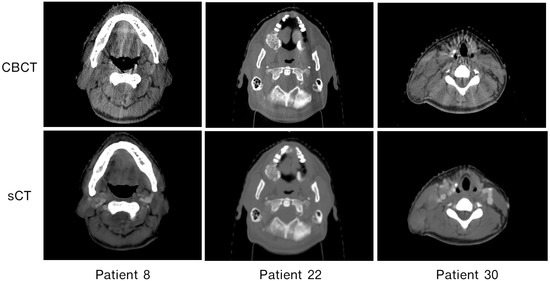

3.3. Patient-Specific Differences